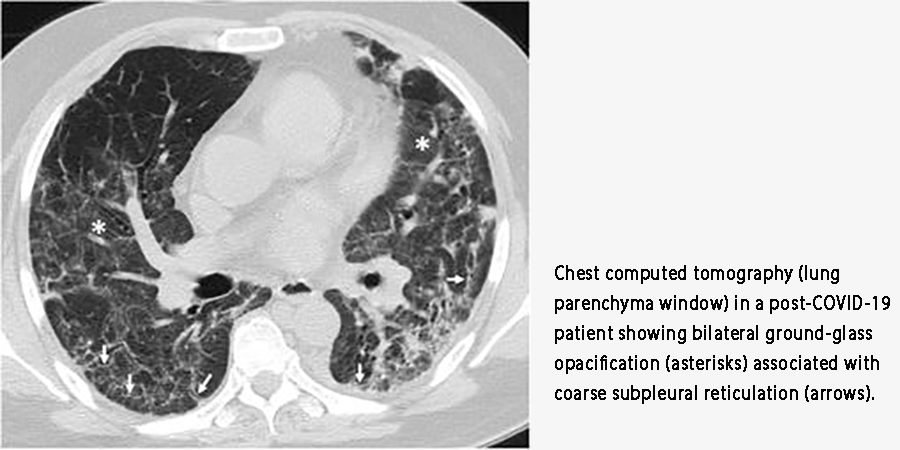

Doctors often see the aftermath on CT scans as “ground-glass opacities”—hazy areas that signal inflammation and damage.